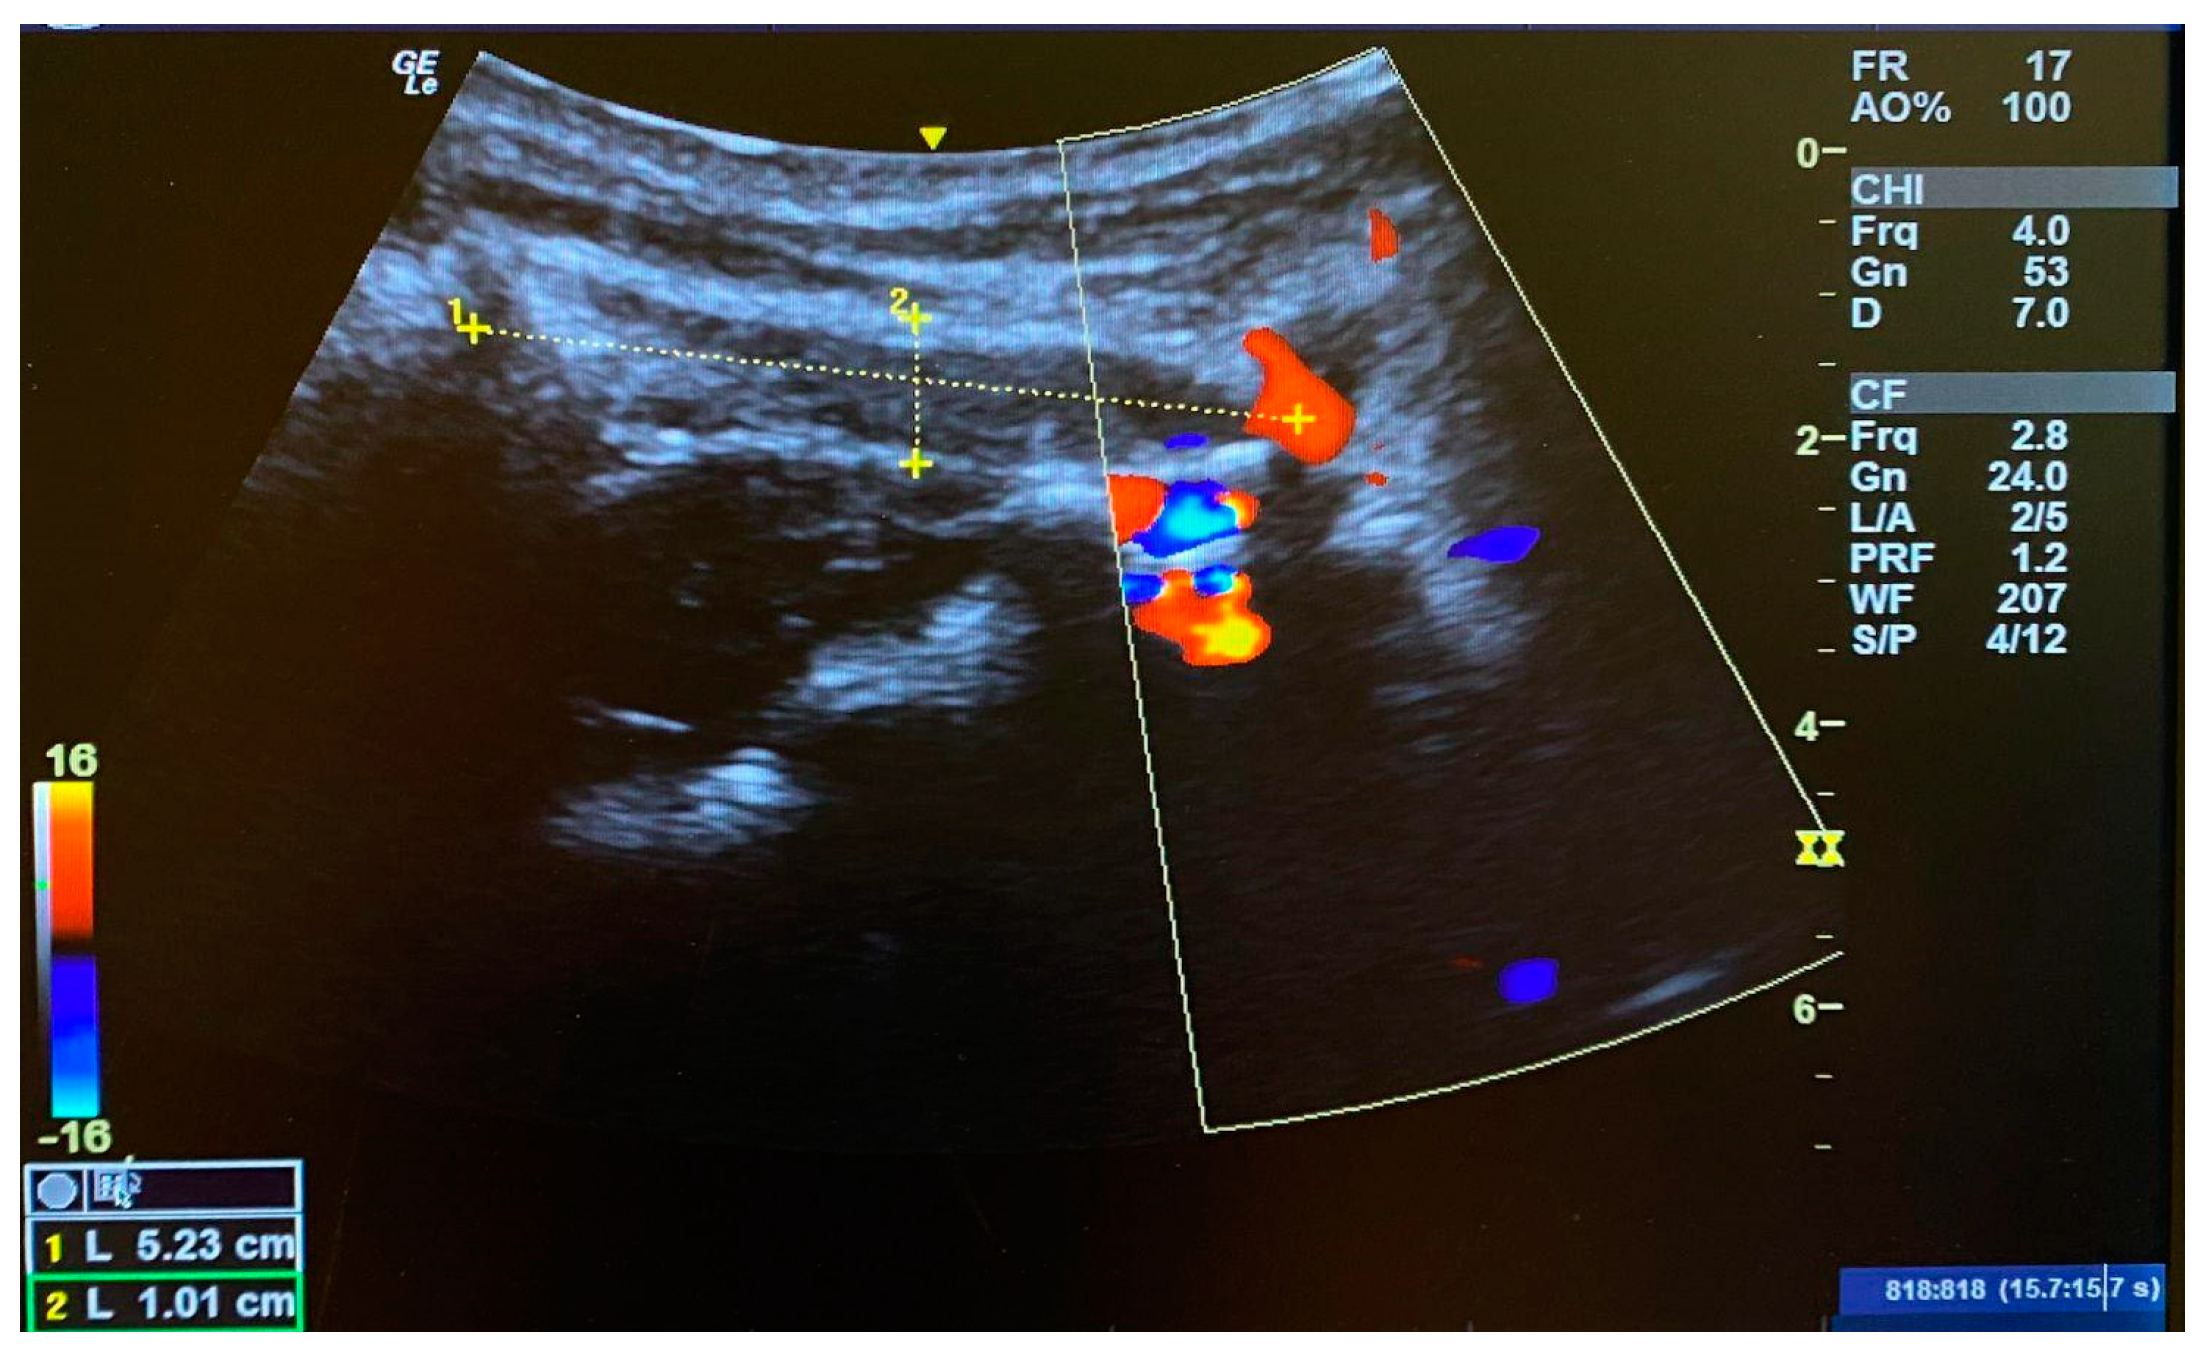

- Sillevis, R.; Swanick, K. Musculoskeletal ultrasound imaging and clinical reasoning in the management of a patient with cervicogenic headache: A case report. Physiother. Theory Pract. 2019, 5, 1252–1262. [Google Scholar] [CrossRef] [PubMed]

- Fernandez-de-Las-Penas, C.; Mesa-Jimenez, J.A.; Lopez-Davis, A.; Koppenhaver, S.L.; Arias-Buria, J.L. Cadaveric and ultrasonographic validation of needling placement in the obliquus capitis inferior muscle. Musculoskelet. Sci. Pract. 2020, 45, 102075. [Google Scholar] [CrossRef] [PubMed]

- Overas, C.K.; Myhrvold, B.L.; Rosok, G.; Magnesen, E. Musculoskeletal diagnostic ultrasound imaging for thickness measurement of four principal muscles of the cervical spine—A reliability and agreement study. Chiropr. Man Ther. 2017, 25, 2. [Google Scholar] [CrossRef] [PubMed]